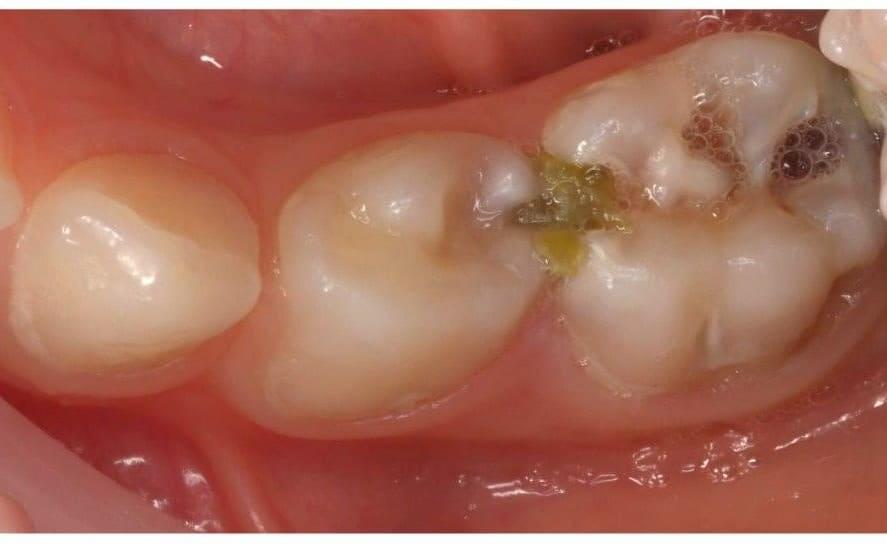

Поява перших постійних зубів, а це шості зуби, відбуваються, коли дитина ще не може, як слід провести їх гігієну та попіклуватись про їх здоров’я. Тому, на жаль вони і вражаються карієсом досить швидко. Пацієнт ще маленький – 6 років, а лікування потребує дорослого: зі знеболенням та ізоляцією. Саме таке і було проведене в даному випадку: зуб очищений від інфікованих тканин, відновлений фотополімерним матеріалом і готовий довго служити юному господарю.